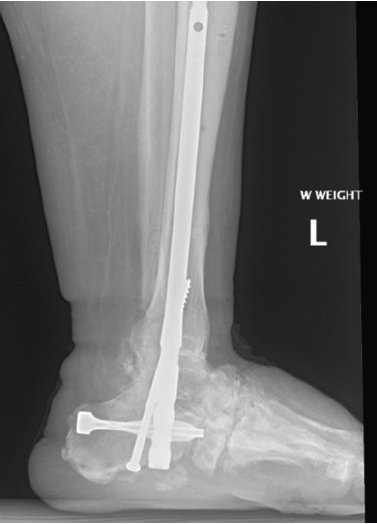

My typical construct for the second stage of midfoot Charcot neuroarthropathy reconstruction is to make the rearfoot and tibia-ankle-calcaneus relationship permanent with a tibiotalocalcaneal fusion (see Figure 5). I place very little midfoot hardware. My preferred method is intramedullary fixation but that varies based on individual patient factors such as old wounds or incisions. For example, if there had been old wounds or infection involving the plantar heel, then I would choose either anterior or lateral plating. The fixation is surgeon-dependent but I feel intramedullary fixation is the most reliable, especially in cases of pseudoarthrosis.